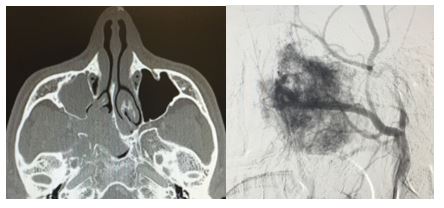

1. 04/2017. Masculino 9 años con obstrucción nasal de inicio gradual, epistaxis recurrente derecha, presentando masa en fosa nasal derecha de 3 años de evolución con extensión a seno maxilar, fosa pterigomaxilar e infratemporal derecha, así como Iisis de piso de orbita. Clasificación IIC (Radkowski) III (Chandler). Se realiza angiografía, embolización desde arteria carótida externa y se realiza resección vía Weber Ferguson, con resección completa del mismo, con buena evolución a 16 meses de posquirúrgico sin recurrencia.

1

2. 08/2017. Masculino 24 años con obstrucción nasal de inicio gradual, epistaxis recurrente bilateral con masa en cavidad nasal bilateral de 3 años de evolución. TC con extensión a naso y orofaringe, maxilar derecho, fosa pterigomaxilar ipsilateral. Clasificación IIB (Radkowski) III (Chandler). Se realiza angiografía, embolización, y resección vía Degloving mediofacial, resección completa, buena evolución a 1 año de posquirúrgico, sin recurrencia.

2